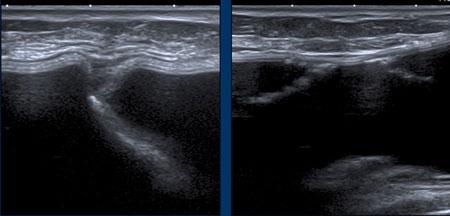

Một lượng nhỏ dịch quanh túi độn không có âm vang (anechoic) là bình thường (hình bên trái).

Lượng dịch tràn ngày càng tăng hoặc dịch có âm vang hơn có thể được chọc hút để xét nghiệm, tùy thuộc vào biểu hiện lâm sàng.

Nếp gấp

Nếp gấp xuất hiện dưới nhiều hình thái khác nhau và có tính chất động.

Khi gấp ra ngoài, chúng đôi khi có thể sờ thấy được, đặc biệt ở các rìa của túi độn ngực và ở những vị trí có ít mô giữa túi độn và da.

Các nếp gấp này là hình ảnh bình thường.

Nếp gấp hướng tâm (Radial folds)

Các đường thẳng hoặc đường cong sâu bên trong túi độn có thể khó đánh giá.

Liệu chúng là các nếp gấp hướng tâm bên trong hay là một phần của vỏ bọc bị xẹp do vỡ túi trong bao xơ? Cần tìm kiếm thêm các dấu hiệu khác và theo dõi đường đi của chúng để xem có liên tục với vỏ bọc hay không.

Trong một số trường hợp, cần chụp MRI để giải quyết vấn đề này.